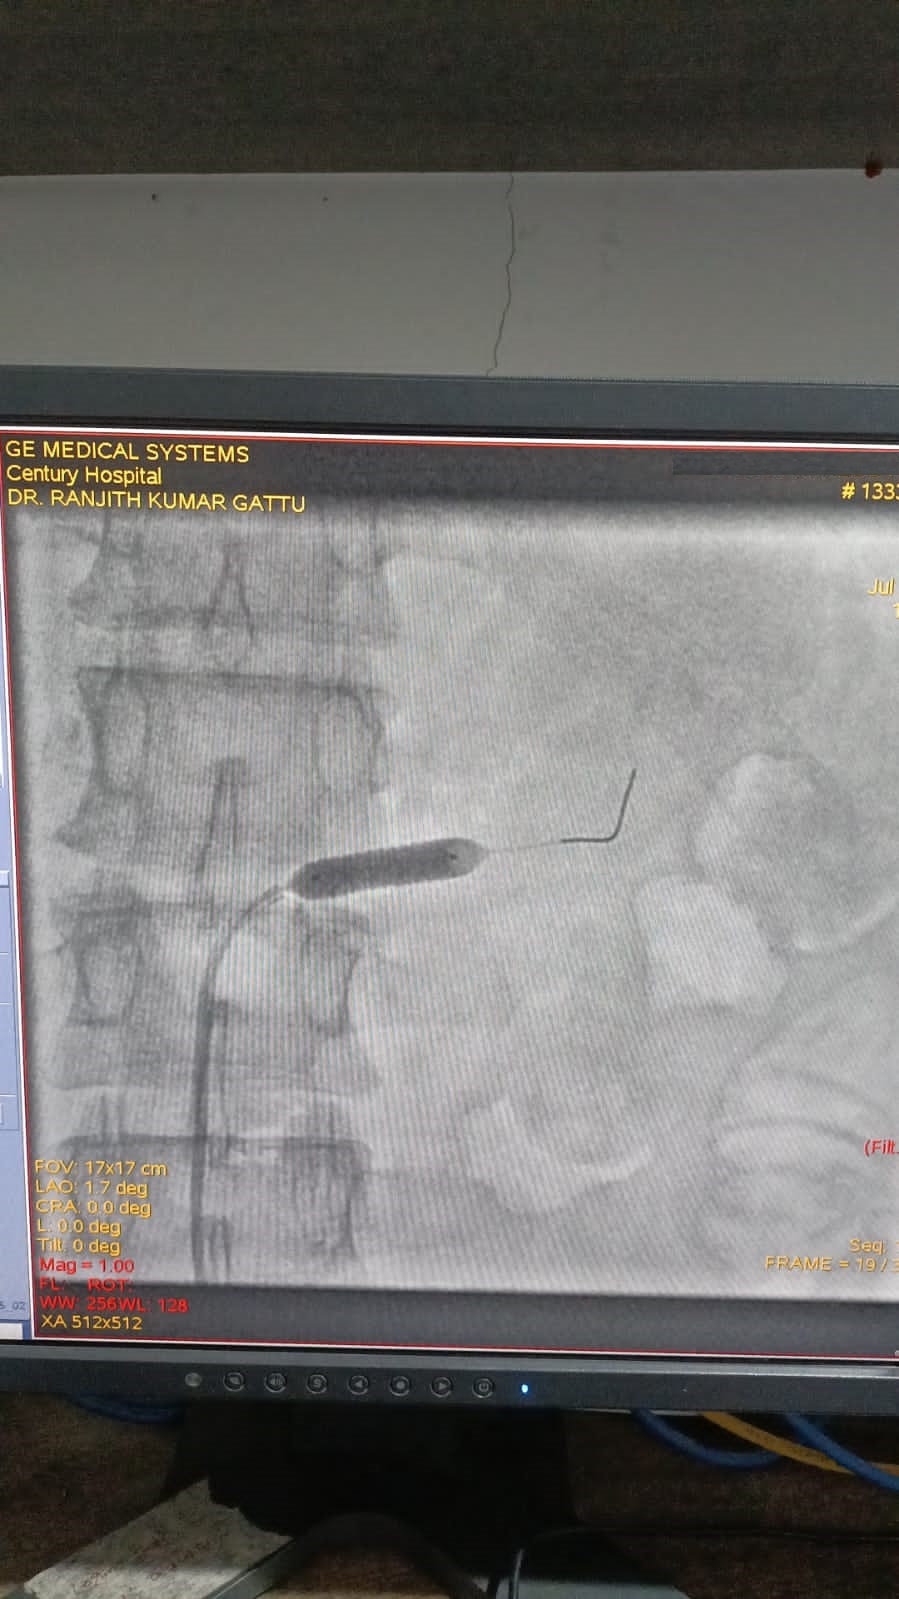

Left Coronary Diseased Artery

Right Coronary Diseased Artery